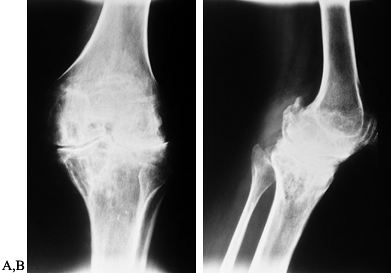

Figure 136.5. AP (A) and lateral (B)

radiographs showing moderately advanced hemophilic arthropathy with almost complete loss of cartilage interval. Note the synovial cyst in the medial femoral condyle, flattening of the anterior part of the trochlea resulting from lateral subluxation of the patella, and loss of the normal posterior tilt of the tibial articular surface, which results from a flexion contracture during growth. These changes are typical of hemophilic arthropathy. |